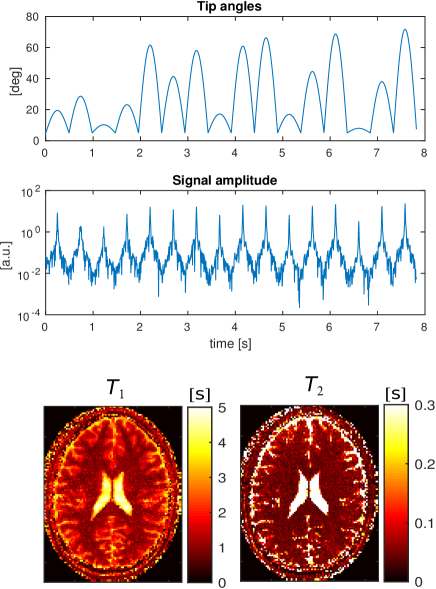

For the acquisition, a Cartesian trajectory is used. The duration of each read out is 0.86 ms with a 4 s dwell time per sample. The read out lines ( direction) cover the 2D -space in ascending order, starting with the smallest negative values of and repeating this pattern for the equivalent of 8 full -space coverages. In total, lines are acquired in 8.3 seconds resulting in approximately time data points. The random tip angles sequence is shown at the top of Fig. 2.

A Gaussian shaped RF pulse and a slice selective gradient waveform along the axis are applied. The RF pulse is 1 ms long and is defined on a ms dwell time step. The slice profile variation throughout the sequence is taken into account by discretizing the spatial domain in the slice-selective direction by 50 points and integrating the magnetization response for each point. This integration is applied to both the forward (signal simulation) and backward (reconstruction) steps. Gaussian noise is superimposed to the time-domain signal such that . The resulting time-domain signal is shown at the bottom of Fig. 2.

During an MR-STAT experiment, the magnetization is thus no longer expected to be in steady-states or equilibrium conditions but is free to evolve. Since there are no particular requirements on the state of the system, the excitation/acquisition scheme can be designed to boost the time-efficiency and to minimize the impact of gradient hardware imperfections. In this work, we consider measurement schemes (sequences) where RF excitation pulses and acquisition intervals are contiguous, thus the repetition time and echo-time are kept as short as possible (see Fig. 1); there are no dead times and the data collection rate is thus maximized. We choose to employ a so-called cartesian read-out scheme which is the standard acquisition modality due to its robustness with respect to hardware imperfections.

To demonstrate the design flexibility of MR-STAT, we employ several types of acquisition schemes: one where the tip angles are randomly drawn from a normal distribution (Fig. 2); one which follows a sinusoidal pattern where each lobe is weighted by a randomly chosen value (Fig. 8-Top) and one with piecewise constant excitations (Fig. 9-Top). For the latter RF-train, each constant tip angle section is preceded and followed by a half-angle pulse acting, respectively, as excitation and tip-back pulses. All the sequences start with a 180o inversion pulse. Each read-out interval is centered between excitations and all gradients are balanced, thus a single isochromat accurately represents the dynamics of a voxel.

We employ two different sequences. The first RF train (Fig. 8, top) consists of 16 sinusoidal sweeps. Each lobe corresponds to a -space filling and is randomly scaled to achieve maximum amplitude levels in the range .